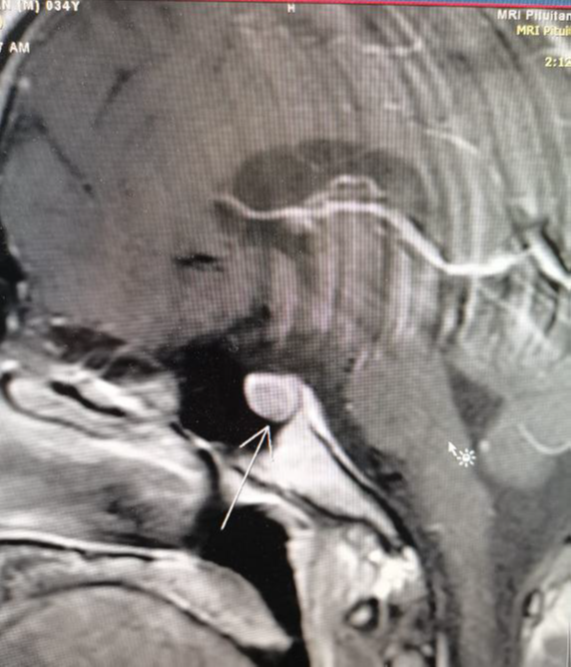

Our patient, Mr. X, a 34-year-old male, was referred to an endocrine clinic (in King Hussain Medical Center) to assess his thyroid status. Upon evaluation, he was anxious and irritated, and his sister said he had some behavioral changes for the last few months. He was usually calm and friendly, she said he lost weight despite his increased appetite. His past medical history was significant for epilepsy and minor cardiac anomalies (atrial septal defect and atrioventricular canal). During examination, he had a small firm goiter with no bruit or thrill on palpation. He also had tremors of outstretched extremities, but no opthalmopathy which can be related to thyroid disorders, galactorrhea, or acromogelic features. His heart rate was 105, and his blood pressure was 127/80. His laboratory investigations showed a thyroid function test (tft) with elevated TSH level 17 (normal range: 0.34–5.6 μU/L) and elevated free thyroxine level 2.46 (normal range: 0.7-1.8 ng/dl). We ran the test again, and it revealed similar readings. Previous thyroid function tests were normal, so a thyrotoxic condition was considered. A beta-blocker was prescribed to the patient, and it had a dramatic effect on controlling his symptoms. Ultrasonography showed a mild goiter with hypervascularity, and the thyroid scintigraphy scan showed thyroid enlargement with hypervascularity (Figure 1), so a diagnosis of hyperthyroidism was confirmed. An auto-antibody panel was sent, and it came back negative. The sex hormone binding protein was a high normal 51.97 nmol/l (range 18.3–54.1), the alpha subunit wasn't done due to unavailability. Growth hormone and prolactin were normal. In addition, pituitary magnetic resonance imaging (MRI) (Figure 2), (Figure 3), (Figure 4) was done, and it showed a microadenoma of 9.9*8.4 mm dimensions with no pressure effect on the pituitary stalk and optic chiasm. He underwent visual perimetry and his visual fields were normal. As we suspected a TSH-secreting pituitary tumor, a somatoastain analogue was given to the patient for both diagnostic and therapeutic purposes.4–7 Tsh level showed significant suppression (15 to 5 normal range: 0.34–5.6 μU/L), four weeks following the somatostatin analogue injection. As surgery is the first-line treatment for Tsh-oma, his case was discussed with the neurosurgeons, and the patient was sent for surgery. Before surgery, his heart rate was controlled by beta blockers, and then he underwent transsphenoidal surgery by an expert neurosurgeon with no significant postoperative complications.8

Figure 1 Sagittal pituitary MRI.